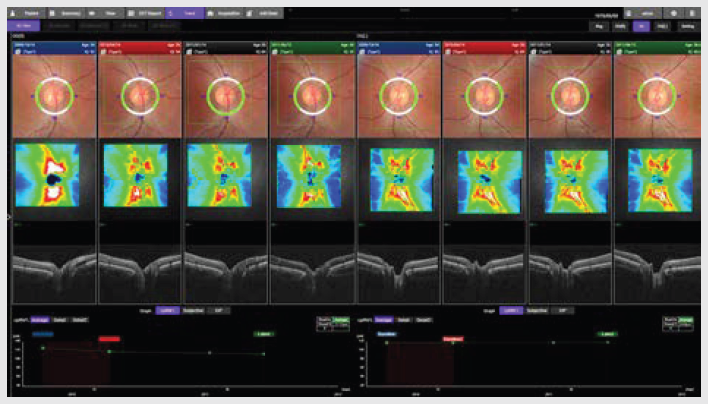

GLAVKOM

*5 Primerjava diagnostične zmožnosti glavkoma med širokopoljskimi zemljevidi RNFL s swept-source OCT in spectral-domain OCT

Won June Lee, Ki Ho Park et al., Eye, letnik 32, 2018

Diagnostična natančnost širokopoljskega zemljevida s swept-source optično koherentno tomografijo pri primarnem odprtokotnem glavkomu pri kratkovidnih očeh

Yong Woo Kim, Jinho Lee, Jin-Soo Kim, Ki Ho Park, AJO, 2020

*6 Donald C. Hood, PhD, Translational Vision Science & Technology, št. 6, letnik 3, 2014: Evalvacija enostranskega poročila za pomoč pri odkrivanju glavkomske okvare.

*7 En sam širokopoljski OCT-protokol lahko zagotovi prepričljive informacije za diagnozo zgodnjega glavkoma

Donald Hood et al., Translational Vision Science & Technology, 2016